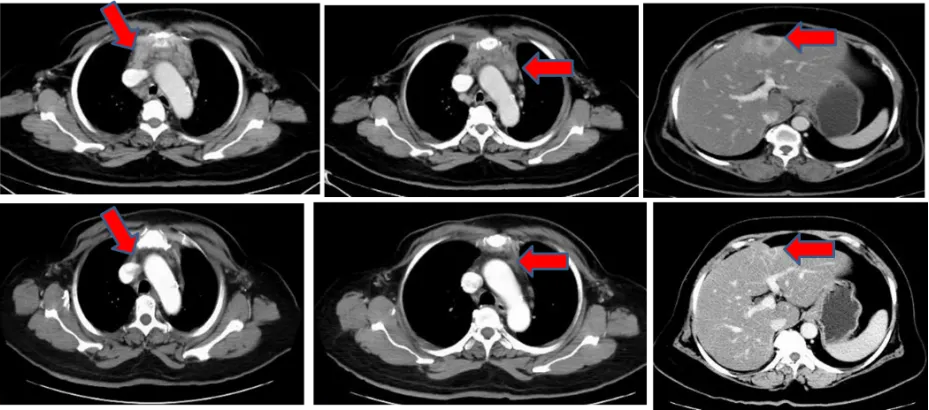

2018年1月,患者出现双侧颈部、双侧锁骨上窝、纵隔淋巴结转移;胸壁、肝多发转移、胸骨转移,为进一步治疗来我院就诊。皮肤活检病理示:真皮浅、中、深层血管、淋巴管内见肿瘤细胞团块,胞核深染,胞浆丰富,部分呈空泡状。符合皮肤转移癌(乳腺来源可能)。免疫组化:ER(-), PR(-), HER-2浸润癌(2+),Ki-67约80%(+),TROP2(约50%中-强+、约20%弱+) ;GATA-3(+),TRPS1(+)。Fish阴性。

诊断:双乳浸润性癌(三阴型);双侧乳腺癌改良根治术后;双侧颈部、双侧锁骨上窝、纵隔淋巴结转移;胸壁、肝多发转移、胸骨转移

图片1.png

图1 2018年1月8日 CT结果